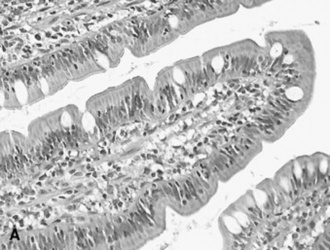

BIOPSY

The decision about whether to obtain a biopsy is often based on the ease of obtaining a sample and the relative value of the evaluation that can be made. Very small samples, such as those obtained with an endoscope biopsy instrument, are relatively easy to obtain, but they provide limited information. Full-thickness bowel specimens, obtained by means of ventral midline or flank laparotomy, are more difficult to obtain, but they provide much more information.

Taking a biopsy sample by endoscopy allows the practitioner to choose the biopsy site on the basis of the appearance of the mucosal surface, which most frequently reflects an inflammatory disorder. Conversely, when a biopsy sample is obtained through laparotomy, the serosal surface of the bowel may not reflect a disorder within the bowel wall. In such instances it may be useful to obtain several biopsy specimens. Rectal mucosal biopsies are easily performed. Many instruments can be used to obtain the biopsy specimen, and a uterine biopsy forceps works well. A fold of mucosa can readily be pinched between two fingers, and a sample of this tissue is obtained. The size of the sample is adequate for histologic or bacteriologic examination.